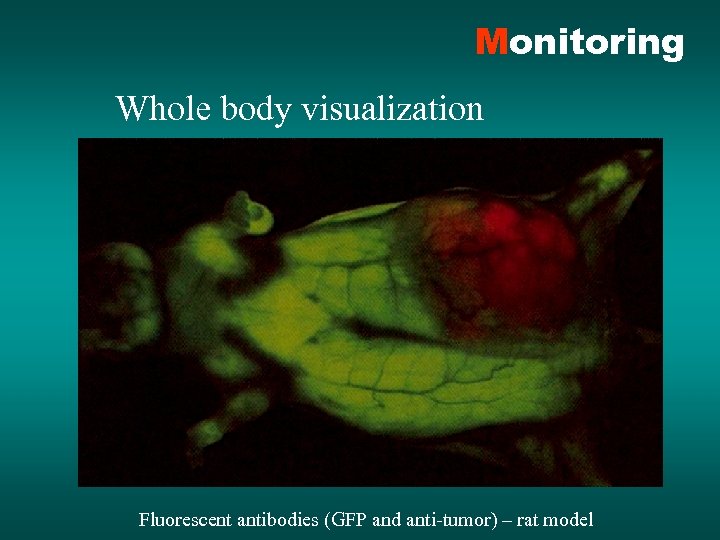

Monitoring Whole body visualization Fluorescent antibodies (GFP and anti-tumor) – rat model

Monitoring Whole body visualization Fluorescent antibodies (GFP and anti-tumor) – rat model

Monitoring Whole body visualization Fluorescent antibodies (GFP and anti-tumor) – rat model

Monitoring Whole body visualization Fluorescent antibodies (GFP and anti-tumor) – rat model